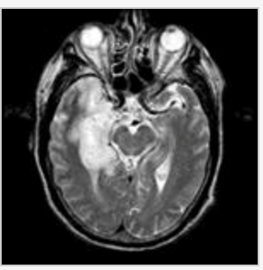

Seven days ago a 3 year old boy developed a low-grade fever which resolved and was followed by a vesicular rash (see Figures). Two days ago, he had sudden onset of truncal ataxia and horizontal nystagmus. He has moderate dysmetria of both arms when reaching for toys, cannot stand or walk, and his speech is slurred. His mental status is fully intact. Fundi show sharp disc margins. His strength is full and deep tendon reflexes are present. What is the MOST likely diagnosis? a. Opsoclonus myoclonus syndrome b. Guillain-Barre Syndrome c. Post-infectious cerebellar ataxia d. Acute disseminated encephalomyelitis e. Posterior fossa mass

c. Post-infectious cerebellar ataxia